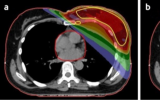

需要放療的乳腺癌患者是否應該選擇質子治療?

英國皇家馬斯登NHS信托基金會、倫敦癌癥研究所的學者發表在BMJ上的一篇研究探討了需要放療的乳腺癌患者是否應該接受質子治療?結果表明,雖然目前沒有隨機試驗數據支持乳腺癌患者常規使用質子治療,但是質子治療可以比X射線放療更準確,減少危及器官如心臟的副作用。 2023-06-14